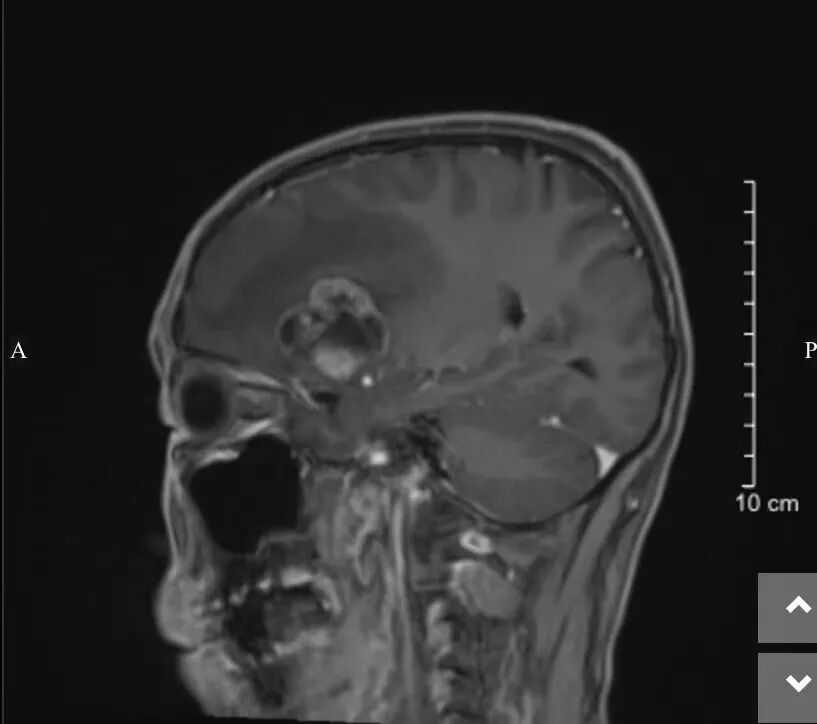

熊洪奇主任醫(yī)師接診后,為何大爺詳細排查病因,CT檢查發(fā)現(xiàn)其右側(cè)額葉占位性病變并右側(cè)額顳葉大片水腫待排。原來,何大爺4年前曾在外院行肺癌手術。結(jié)合病史查體,考慮肺癌腦轉(zhuǎn)移的可能性比較大。

神經(jīng)外科團隊就何大爺?shù)那闆r制定了精細的治療方案。術前,通過問病查體、仔細閱片、綜合利用CT及MR影像資料詳細評估了患者的腦部病變。熊洪奇主任醫(yī)師介紹:“顱內(nèi)病變位于右側(cè)額葉,腦水腫嚴重,顱內(nèi)壓力高,中線已經(jīng)明顯偏移,考慮腦轉(zhuǎn)移瘤可能性大。目前已經(jīng)出現(xiàn)持續(xù)頭痛癥狀,如不及時處理顱內(nèi)病灶。因為病情繼續(xù)發(fā)展,患者很可能出現(xiàn)腦疝、意識不清、危及生命,手術指征明確,手術目的一是切除病灶,解除顱內(nèi)高壓,搶救生命;二是明確病理診斷,為后續(xù)治療提供依據(jù)?!?/span>

術后,何大爺在ICU觀察了1天后轉(zhuǎn)入普通病房。術后第9天,何大爺頭痛頭暈癥狀明顯改善,可行走自如,對答如流,神經(jīng)功能保護滿意,復查影像資料提示病灶切除,達到預期治療效果。經(jīng)過一段時間的精心治療,何大爺目前已經(jīng)康復出院。

神經(jīng)外科主任熊洪奇介紹,由于患者腦部腫瘤為邊界欠清的腦轉(zhuǎn)移瘤(肺癌),位于前顱底,位置較深,周圍有許多重要血管且解剖復雜,導致手術難度和風險極大。